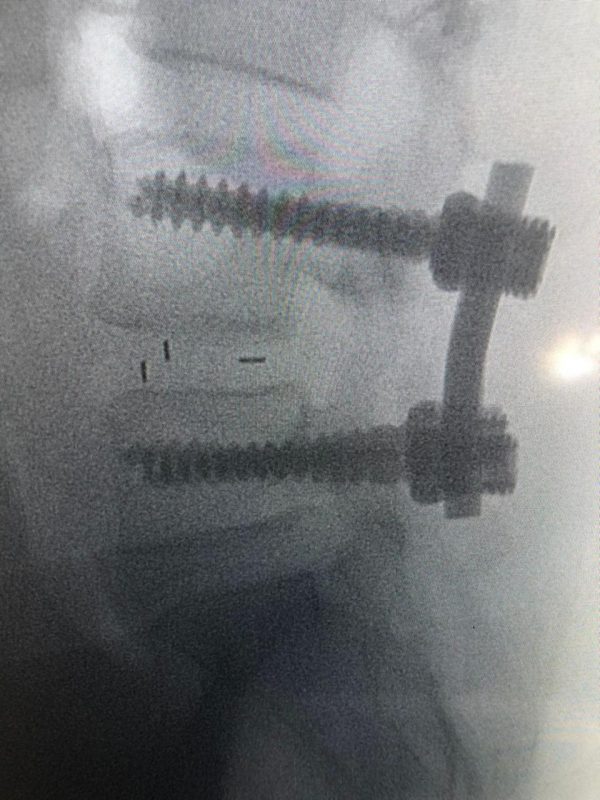

نجح فريق مسار العظام بتجمع الرياض الصحي الأول، من إجراء عملية جراحية معقدة بالعمود الفقري لسيدة خمسينية لا تستطيع الحركة، وذلك بقيادة استشاري جراحة العظام والعمود الفقري د. متعب أبو الراس بمستشفى الملك سلمان بالرياض.

تفاصيل الحالة المرضية

وأوضح د. متعب أبو الراس أن تفاصيل الحالة للمريضة كانت تشكو من آلام مزمنة في الظهر وتمتد إلى الأطراف السفلية مما تؤدي إلى إعاقة قدرتها عن الحركة أو حتى الوقوف، وبعد عمل الفحص الإكلينيكي والأشعة اللازمة تبيّن أن المريضة تعاني من “حالة انزلاق فقاري مصحوب بانزلاق غضروفي وضيق في القناة العصبية بين الفقرتين الرابعة والخامسة القطنية” مع ضرورة التدخل الجراحي.

وأضاف د. أبو الراس بأنه تم إجراء العملية الدقيقة بعد موافقة المريضة عليها وعلى الخطة العلاجية ما بعدها، وتمثلت العملية في توسيع القناة العصبية واستئصال الغضروف ووضع دعامة بين الفقرات مع تصحيح الانزلاق الفقاري وعمل دمج بين الفقرتين الرابعة والخامسة، وتكللت العملية بالنجاح -ولله الحمد- واستطاعت المريضة المشي في أول يوم لها بعد إجراء العملية.